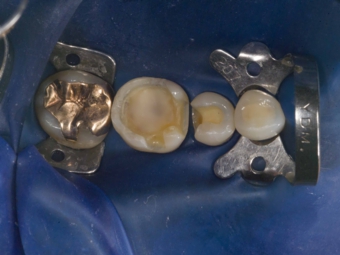

ラバーダム防湿

歯にラバー(ゴムの一種)で出来たマスクのようなものを装着し、唾液等による汚染から隔離します

ラバーダム防湿を行うメリット

1)歯だけが露出させるため、頬の内側の肉や舌などが施術を阻害しなくなるので、安全で精密な施術を行える

2)小さな器具を飲み込まないようにできる

3)根管治療をより無菌的に施術できる。

上記の中で3)が最も重要です。というのは口腔内には350種類以上の常在菌がいると言われています。難治性の根尖性歯周炎(なかなか治らない、もしくは何度も再発する根の治療の予後不良なもの)の原因菌のほとんどはこの口腔内常在菌であるというデータがあります。つまり、根管治療中に唾液が入る事はもってのほかであるということです。根管の中は生体でいえばお腹の中と同じような清潔な場所であるべきであり、ラバーダムを行わずに唾液が流れ込むような状態で根管治療を行うという事は、例えとして公園の砂場で開腹手術(盲腸の手術等)を行っておるのと同じくらい不潔で、医療としてあるまじき不潔さであると考えています。なぜ昔根の治療をした歯が根の先が膿んでしまったりして治療のやり直しが必要になるのか考えてみると、